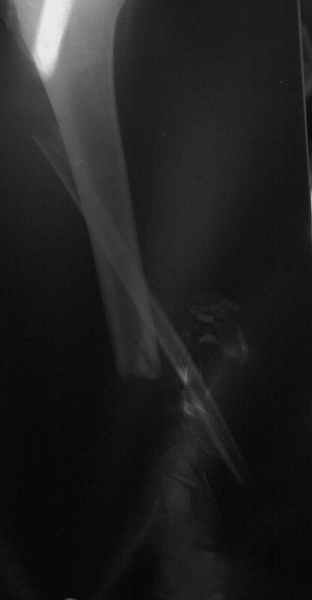

Dorogie kollegy, Have a nice day, Ja bi hotil obsuzdat' s Vami dvuh bolnih, kotorie postupili segodnjia ko mene. Pervy iz nih (OI) bolnoi s otkritoi tiazeloi mehanicheskoi travmoi Rt. leg segment v rezultate DTP, ot chego on imeet sledueshie povrezdenjia: - Otkrity perelom kostei pravoi goleny v srednei i niznoi ee trety s poteriem okolo 10 cm. kostnogo veshestva ot bolshebersovoi kosty, - Povrezdenjia a.tibialis post. s massivnim povrezdeniem zadneoi gruppy musculs goleny, - Malobersovjia kost' imeet segmentarny perelom, ee nizny fragment (kak Vi videte na foto) vistupaet na kozy okolo VNUTRENNOI Lodizky! - Traumaticheski Shock 2-3 Drugih povrezdenjia net.

Nemedlenno bolnoi bil' intubirovan i provedeny vse protivoshokovie procedury, pravjia golen' bila pomeshenjia na apparat' Storm, dla reduksii kostei posle ee fiksasii k apparatu s pomoshio 2 spitsy 3mm D. Provedena Repozitsia pereloma i fiksirovana STORMOM vremenno, za tem sosudisty hirurg vypolnil 2 obhodnih anastomosa for a. Tibilis posterior, bili udaleny bolshie chasty iz musculov zadnoi gruppy goleny v predelah "vozmozno vedemih" zdorovoi tkany, oblast' pereloma promita by N. sol. 0.9% - 12 L. Zatem byla proizvedena okonchatenjia reduksia pereloma posle umerennoi traksii goleny na apparate, i fiksasiya pereloma s pomoshio apparata vneshnei fiksasii. Tak, Kakie soobrazanjia po dalneshemu vvdenjia bolnogo? On poluchaet antibiotiky i bolshie dozy LMH (Clexane 80 X 2) i vse ostalnoe......